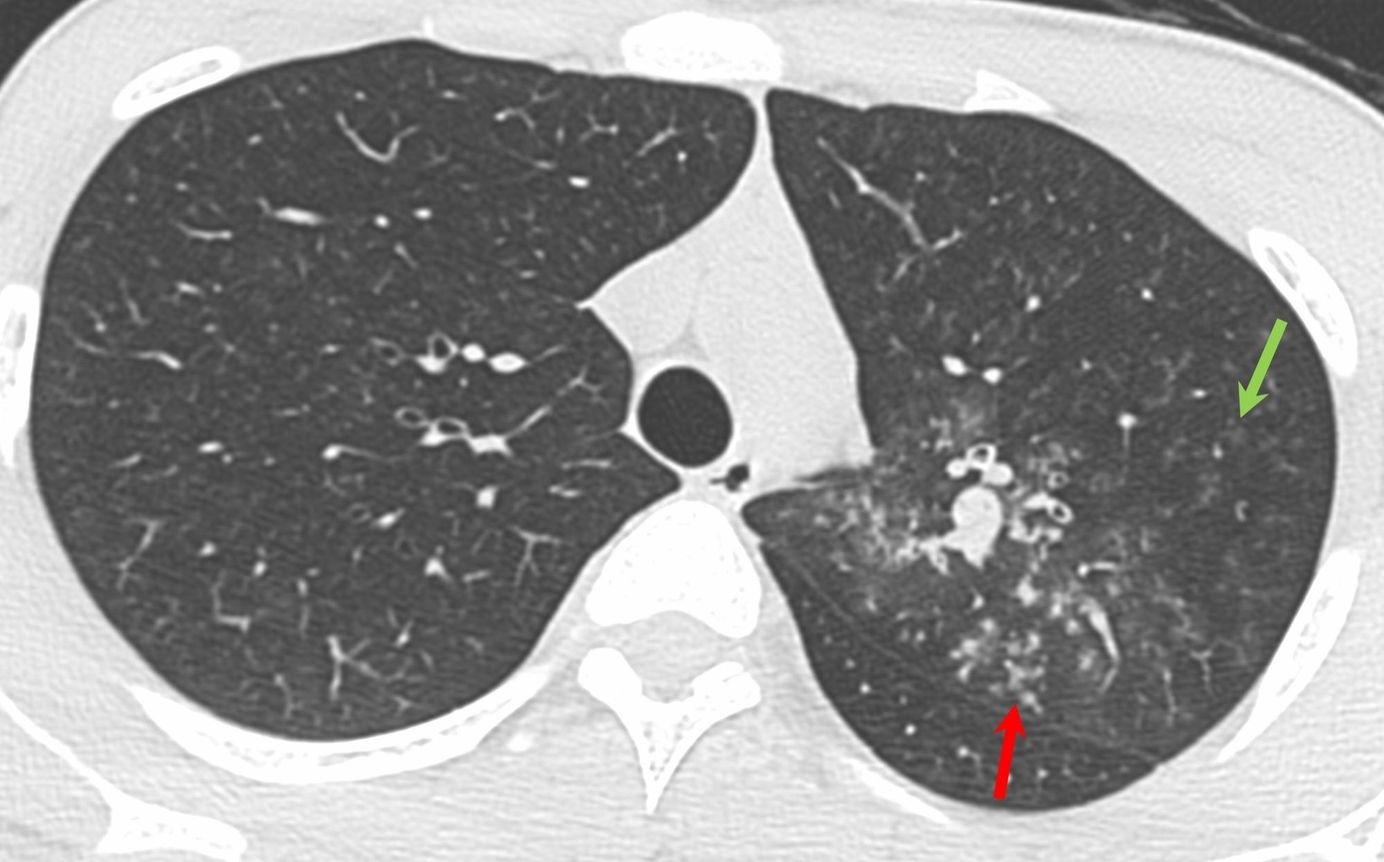

Case 17: Tuberculosis and Hemoptysis - Dense and Soft Centrilobular Nodules Together Members Public

17-years old with tuberculosis and hemoptysis - dense and soft centrilobular nodules together.